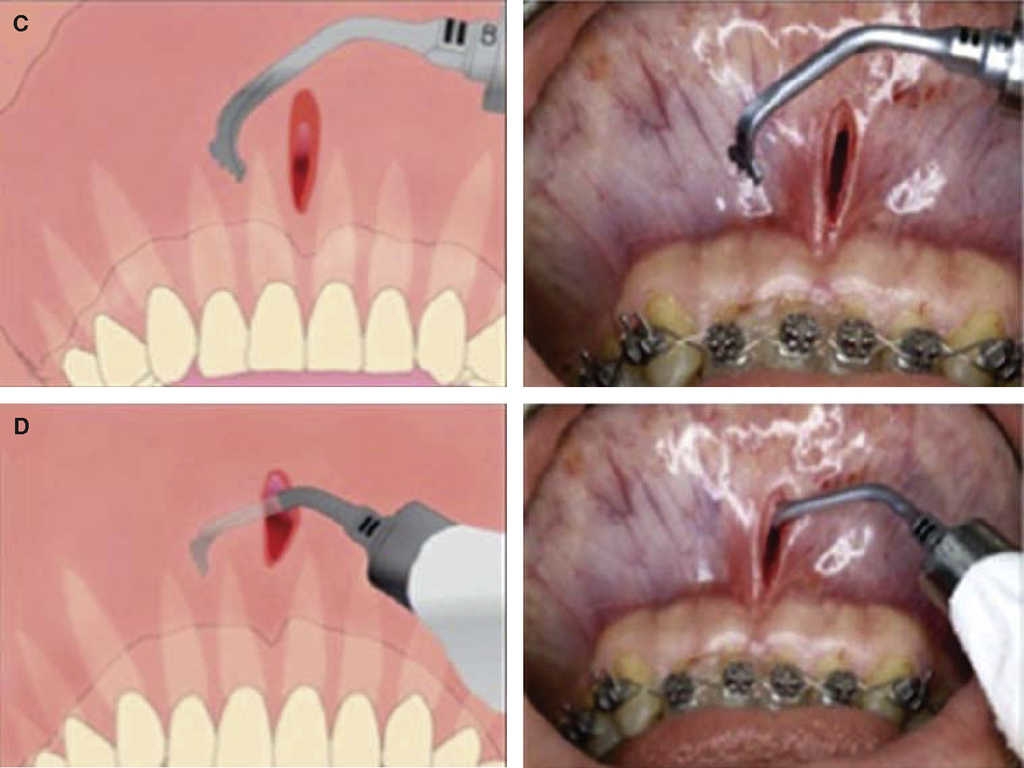

Piezocision technique1 (Dibart 2009)

In 2009 Dibart published a trans-mucosal corticotomy technique called piezocision. It is considered less invasive than the others while providing the same results. It decreases orthodontic treatment time in patients with reduced or intact periodontium, and achieves better results with less aggressive procedures.

In this surgical technique, vertical mini-incisions are performed with a number 15 scalpel micro-blade in vestibular inter-radicular spaces located from the base of the papilla, after this, trans-mucosal corticotomies are performed through previously executed incisions, at a 2 to 3 mm depth. It is not necessary to suture unless there was previous tunnel-building for bone implant placement. Orthodontic forces are applied every 14 days (Figure 14).

The advantage of this technique is that it is minimally traumatic, therefore post-surgical presence of pain, inflammation and ecchymosis is infrequent, since no full-thickness flap was previously raised1 2 and surgical time was short. This technique decreases damage to osteocytes and allows bone cell survival.1 One of the most important advantages of this technique is that the use of electrical scalpel, due to its micro-vibration, allows selective cutting of mineralized structures without damaging soft tissues. This is due to ultrasonic vibrations of 29 kHz frequency and 60/200 Hz range. Micro-metric vibration guarantees precise cutting (Figure 15).1 This technique suffers the disadvantage of allowing poor visibility, unavoidably requiring electrical scalpel use, and diffi culties inherent to control bone graft.2